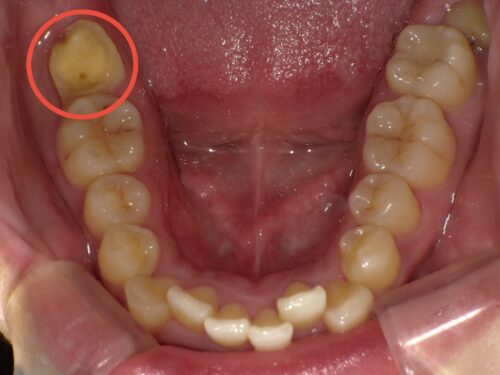

赤い円で示しているところです。この歯が破折してしまいました。

その2日後です。赤い円で囲んでいるのが抜歯予定の歯です。

赤い円で囲まれた部分に上顎の親知らずが存在していることが確認できます。